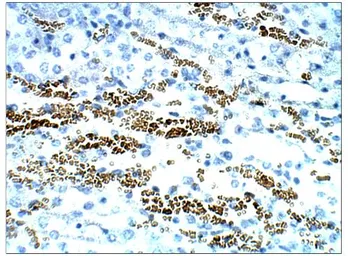

STRA6 antibody

Cat. No. GTX47858

ApplicationsWB IHC-P IP ELISA